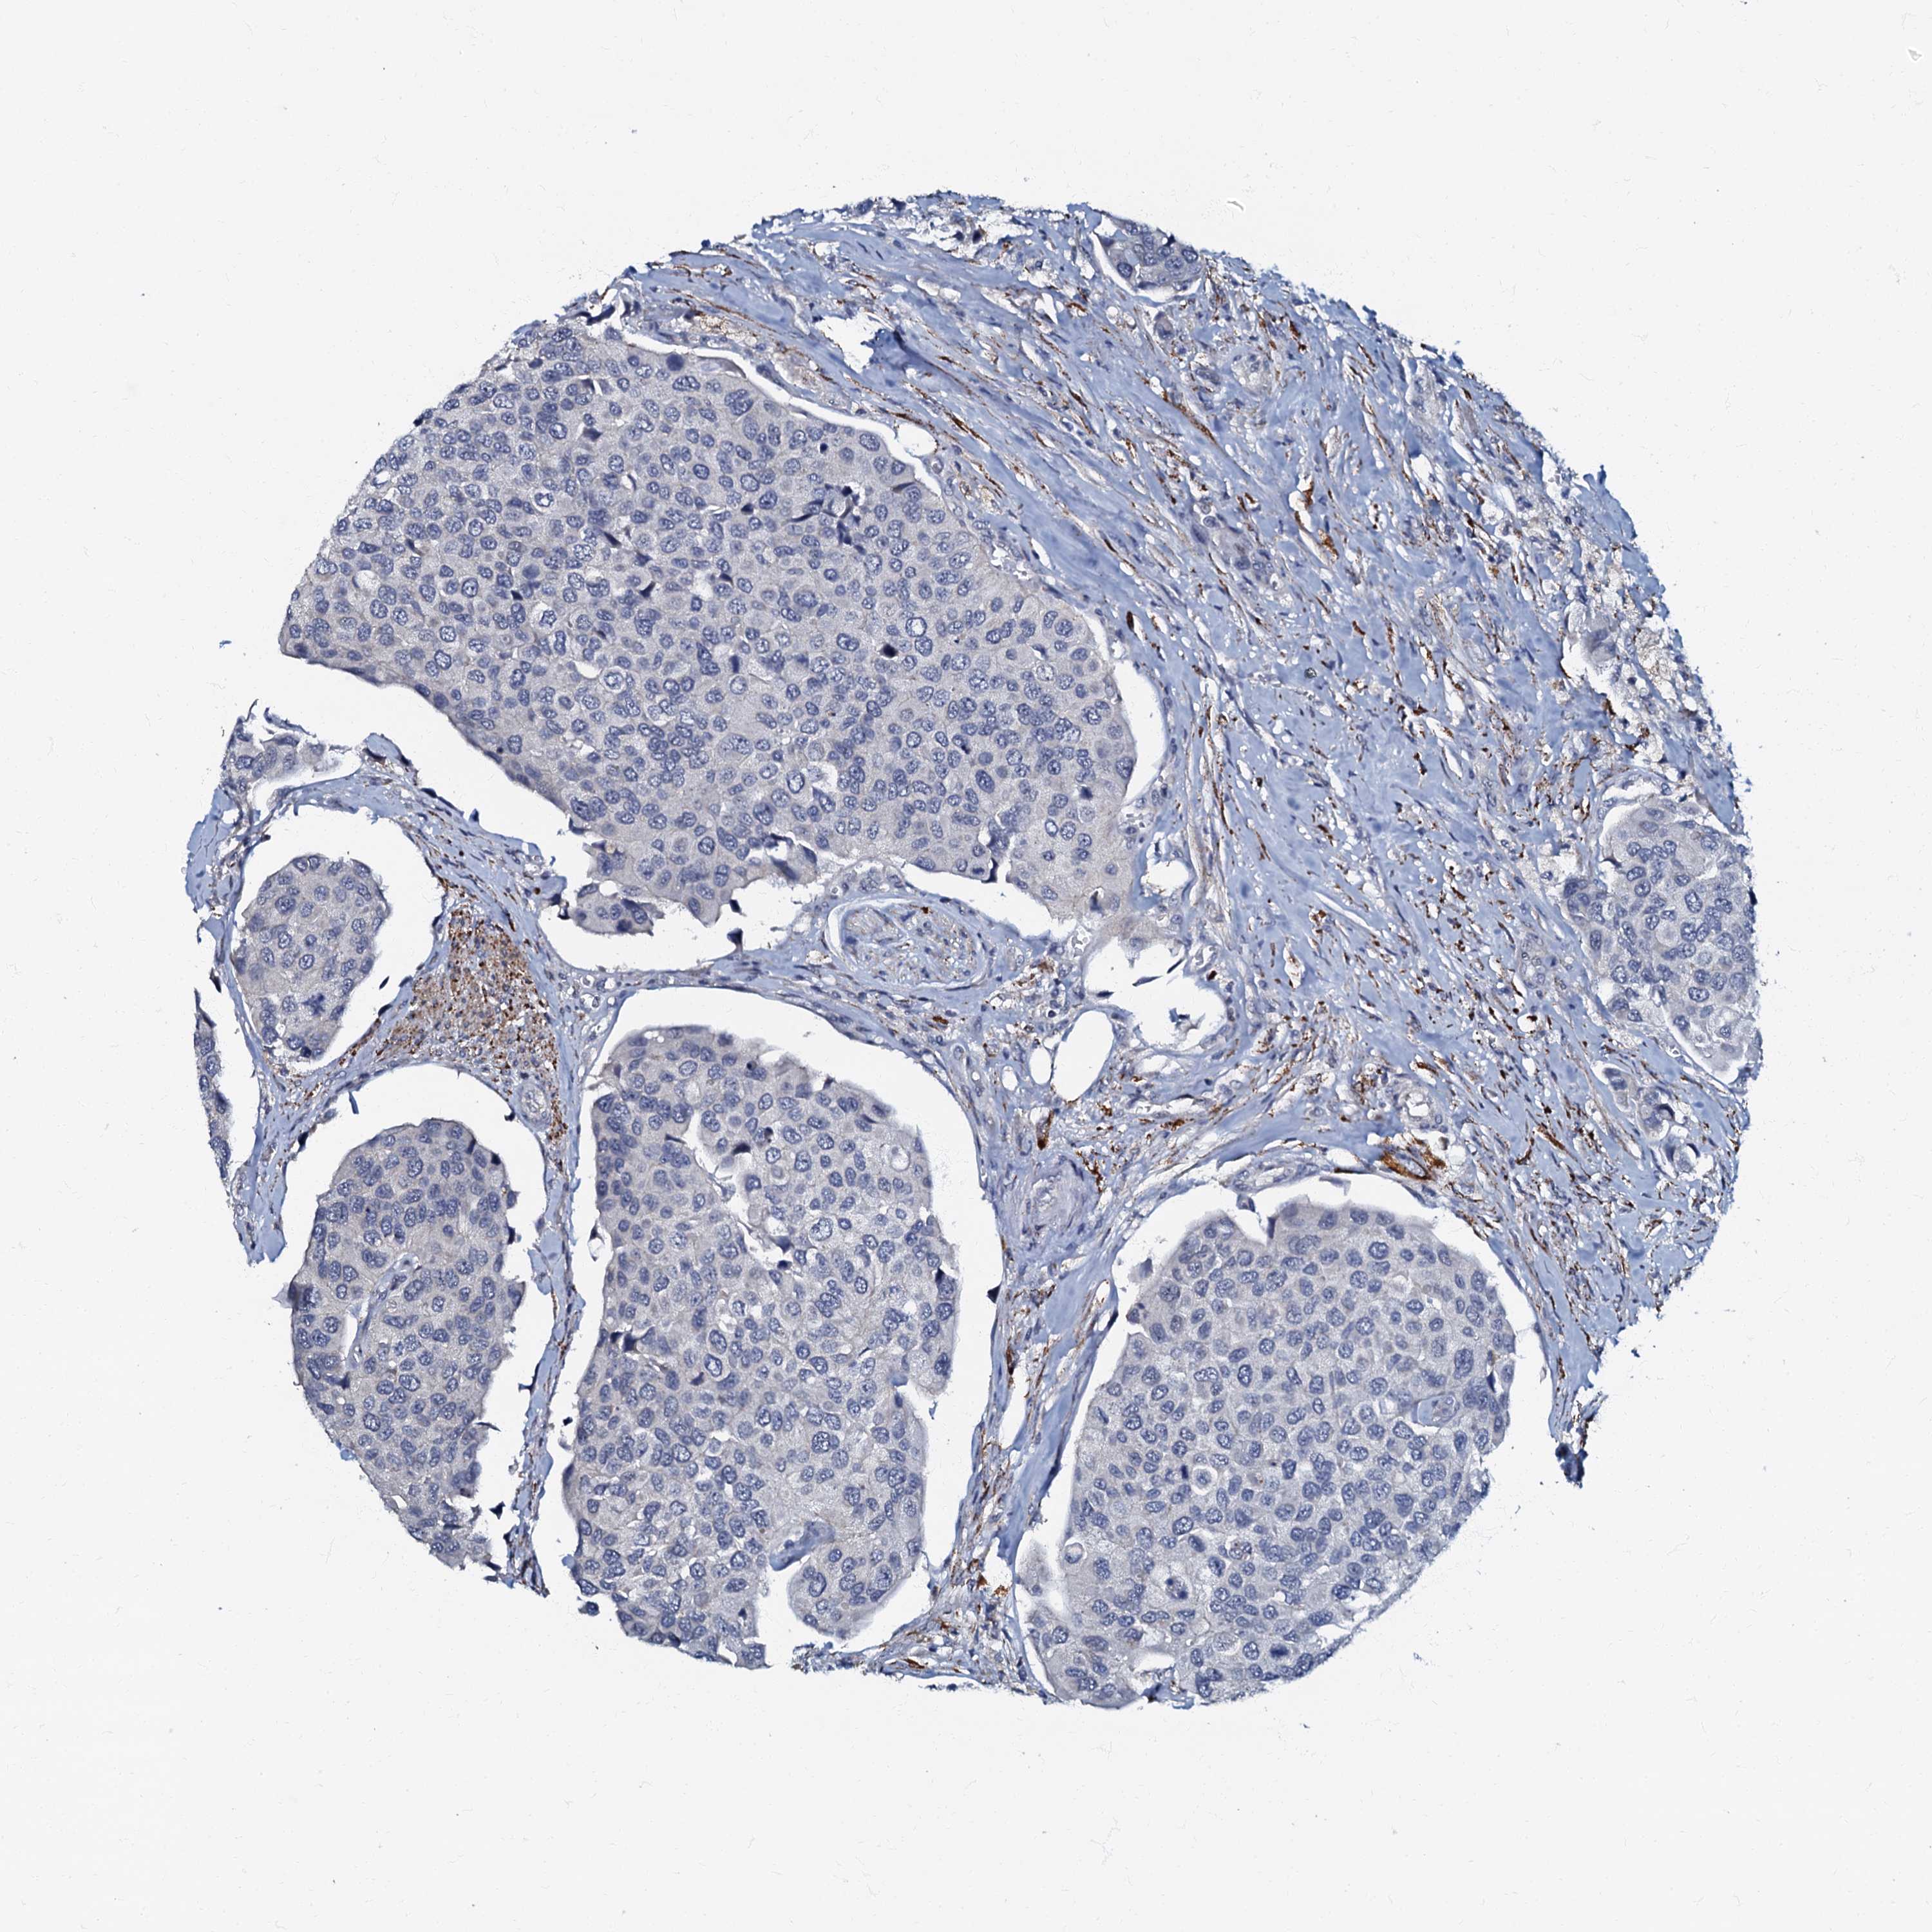

UROTHELIAL CANCER - Protein expressioni

A mouse-over function shows sample information and annotation data. Click on an image to view it in a full screen mode. Samples can be filtered based on level of antibody staining by selecting one or several of the following categories: high, medium, low and not detected. The assay and annotation is described here.

Antibody stainingi

Antibody staining in the annotated cell types in the current human tissue is reported as not detected, low, medium, or high, based on conventional immunohistochemistry profiling in selected tissues. This score is based on the combination of the staining intensity and fraction of stained cells.

Each image is clickable and will lead to virtual microscopy that enables deeper exploration of all samples and also displays staining intensity scores, fraction scores and subcellular localization as well as patient and tissue information for each sample.

Antibody HPA037947

Antibody HPA037948

Urothelial carcinoma, High grade

Urothelial carcinoma, Low grade

Urothelial carcinoma, NOS